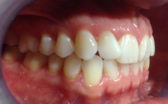

Whilst being fairly happy with my smile, I have always wanted to have perfectly straight upper and lower front teeth. There was some overlap of my upper lateral incisors (the teeth next to the front teeth) over my front teeth. My lower front teeth overlapped each other and were a bit crowded. I did not want to have a long course of braces to correct this, so Cfast sounded like a good option for me.

- Before